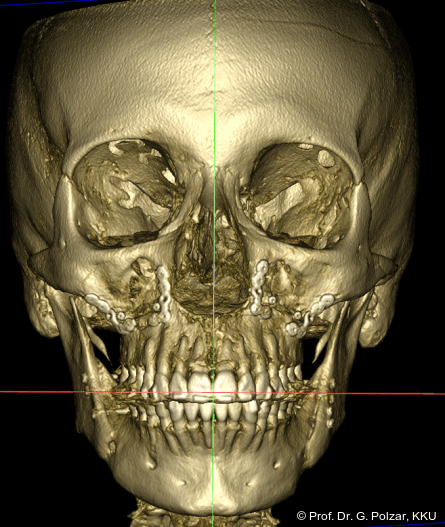

In der Frontalansicht ist eine leichte links-laterale Abweichung des Unterkiefers von der Schädelmitte zu erkennen (Abb. 29). Nach chirurgischer Analyse wurde die Laterognathie weitgehend ausgeglichen und der UK in CranioPlan zentrisch ausgerichtet (Abb. 30a–c).

Da sich die Patientin mit der Operation auch eine Abflachung des Gesichts mit prominenterem Kinn erhoffte, wäre ein deutlich moderaterer CP-OKL-Winkel wünschenswert gewesen. Dies hätte durch eine Intrusion des anterioren Teils der Maxilla und eine deutlichere Counterclockwise Rotation der Mandibula erreicht werden können (Abb. 31)